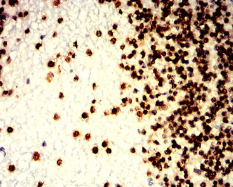

IHC    1/200 - 1/1000